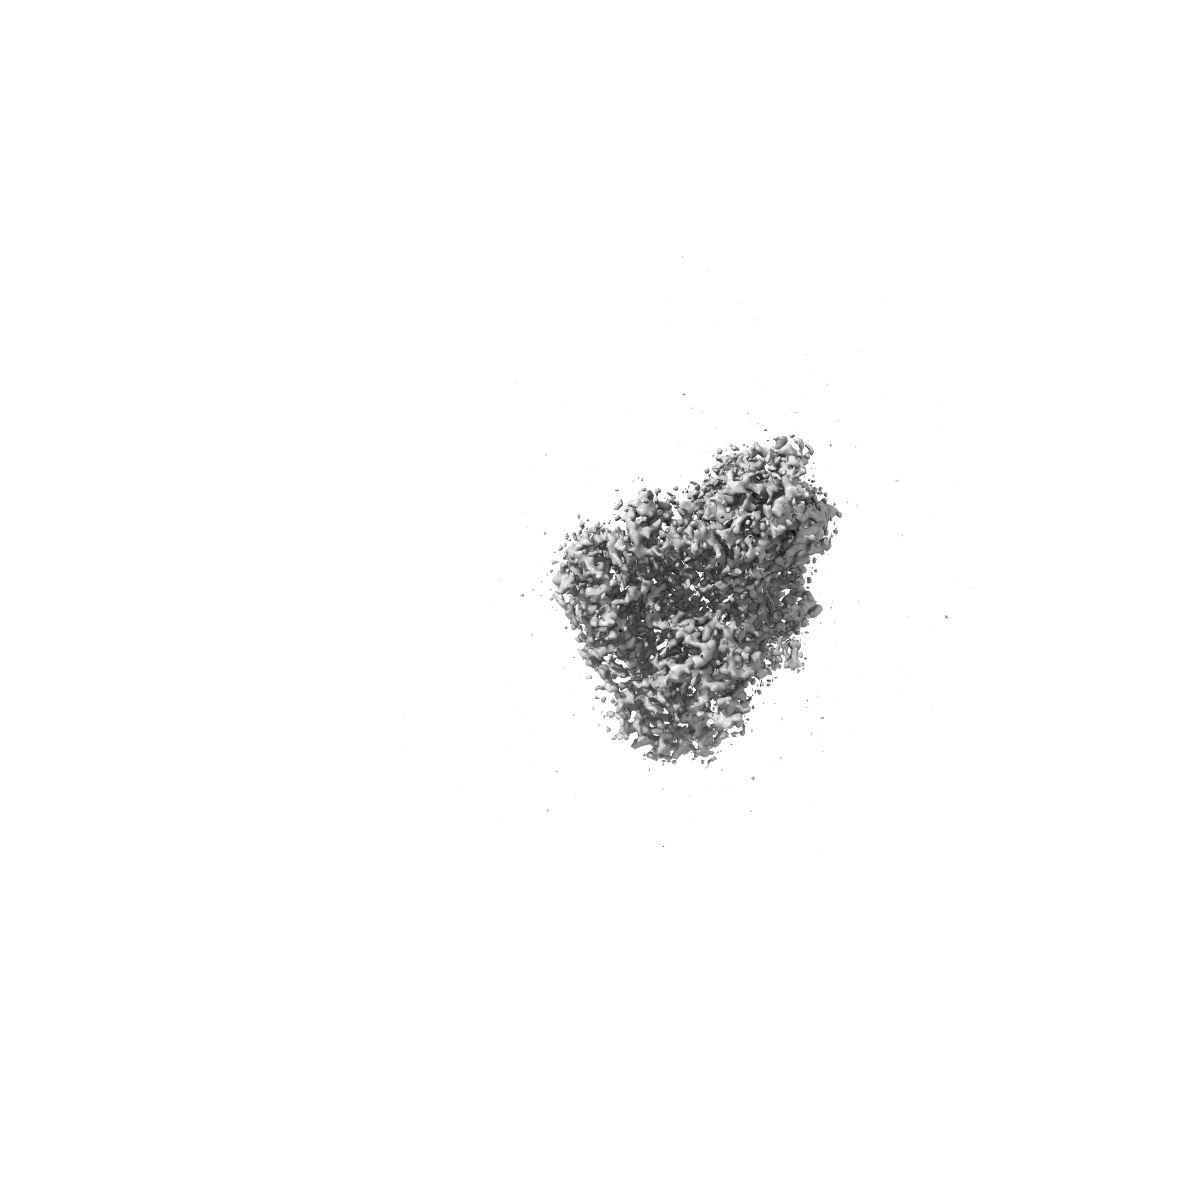

Cryo-EM structure of CAK in complex with inhibitor ICEC0510-S

EMD-17513

Single-particle2.0 Å

Sample: CDK-activating kinase

High-resolution cryo-EM of the human CDK-activating kinase for structure-based drug design.